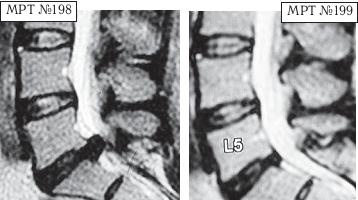

Напомню, что в большом спорте есть большая проблема — это допинги. Допинг в переводе с английского слова «doping» (от dope) означает «давать наркотики». По сути, это в основном химические препараты (фармакологические и другие средства), способствующие стимуляции физической и нервной деятельности на непродолжительное время. Иногда ими пытаются искусственно усилить физическую активность и выносливость спортсмена на время спортивных соревнований. В зависимости от специфики спортивной деятельности в качестве допинга могут использоваться, например, симпатомиметические амины (эфедрин, амфетамин, метиламфетамин и т. д.), стимуляторы центральной нервной системы и восстанавливающие, укрепляющие аналептики (трансамин, стрихнин, лептамин и т. д.), общестимулирующие средства (препараты лимонника китайского, женьшеня, левзеи и т. д.), этиловый алкоголь, наркотики, болеутоляющие средства (морфин, его производные, опиум) и другие препараты. Многие специалисты, не понаслышке знакомые с проблемами большого спорта, отмечают, что современный большой спорт — это уже не старый добрый спорт, где люди показывали свои физические достижения, а это уже во многом соревнование биохимиков по созданию лучшего допинга. Хотя с данной проблемой постоянно борется на международном уровне Всемирное антидопинговое агентство (ВАДА) — независимая организация, созданная при поддержке Международного олимпийского комитета (МОК), каждый год ужесточая антидопинговый контроль, однако всё равно каждый год фарминдустрия выдаёт новые «сюрпризы»-препараты. Печально то, что все эти химические допинги, которые тайно принимает спортсмен для одномоментного улучшения результата, неизменно отражаются на его здоровье, нанося ему ущерб. Ведь весь этот процесс носит экспериментальный характер, а это значит, что последствия для организма вполне могут стать необратимыми, а в некоторых случаях дело может закончиться и летальным исходом, что неоднократно случалось в практике большого спорта. Однако мало кто из спортсменов задумывается в момент приёма допинга о его отдалённых последствиях для своего организма. Многие спортсмены находятся в плену ошибочных стереотипов, которые гласят, что «если не будешь принимать допинг, не сможешь победить». Однако не зря говорится: «Познай себя и ты познаешь весь мир». Возможности человеческого организма многократно превышают возможности искусственной химии. Свидетельством тому является множество известных науке случаев, связанных как со спортом, так и с жизненными обстоятельствами, когда человек в экстремальных, чрезвычайных ситуациях способен проявить такие феноменальные способности и возможности, которые не всякий чемпион сможет повторить. Человеческий мозг — это далеко не изученная, сложная система центрального управления организмом, которая может функционировать в разных режимах, о чём неоднократно упоминается, например, в работах академика Натальи Петровны Бехтеревой. Так что не стоит искать обманчивых путей для достижения высот, ведь ничто не проходит в этой жизни бесследно. Как писал Омар Хайям: «Нищим дервишем ставши — достигнешь высот. Сердце в кровь разорвавши — достигнешь высот. Прочь, пустые мечты о великих свершеньях! Лишь с собой совладавши — достигнешь высот». Так что в любом деле важна внутренняя составляющая человека. Ради справедливости должен заметить, что среди моих пациентов, помимо спортсменов, немало просто самодисциплинированных людей, которые в полной мере ответственно, целеустремлённо подходят к вопросам своего здоровья. Это радует, поскольку понимаешь, что твой труд не пропадёт даром. Ведь если пациент столь тщательно будет следить и беречь своё здоровье и дальше, то организм ещё долго послужит ему верной службой. А это в свою очередь означает, что в жизни данного человека станет намного меньше проблем и он получит полноценную возможность для самореализации. Как говорится в пословице: «Жизнь дана на добрые дела». А тем читателям, кто на сегодняшний день обременён проблемой заболевания позвоночника, хочу сказать, что не стоит отчаиваться. Люди справлялись ещё и с худшими ситуациями. Доказательством тому служат как вышеизложенные, так и нижеприведённые случаи, которые даже высокопрофессиональным специалистам когда-то казались безнадёжными. Думаю, комментарии здесь излишни. Пример № 1. ![]() На МРТ № 192 наблюдается состояние поясничного отдела позвоночника: рецидив после операции — секвестрированная грыжа межпозвонкового диска в сегменте LIV-LV, абсолютный стеноз спинномозгового канала. На МРТ № 193 — состояние поясничного отдела позвоночника после лечения методом вертеброревитологии. Пример № 2. ![]() На МРТ № 194 наблюдается состояние поясничного отдела позвоночника после трёх операций: рецидив — грыжа межпозвонкового диска в сегменте LV-SI стеноз спинномозгового канала. На МРТ № 195 — состояние поясничного отдела позвоночника после лечения методом вертеброревитологии. Пример № 3. ![]() На МРТ № 196 наблюдается состояние поясничного отдела позвоночника после операций: рецидив грыжи межпозвонкового диска в сегменте LV—SI с формированием секвестра с миграцией в краниальном направлении, абсолютный стеноз спинномозгового канала. На МРТ №s197 — состояние поясничного отдела позвоночника после лечения методом вертеброревитологии. Пример № 4.